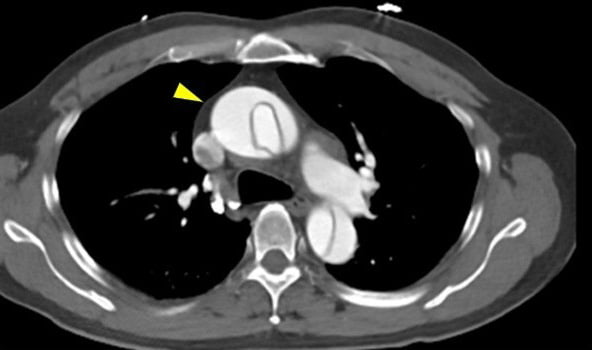

Stanford A型急性大動脈解離の造影CT検査画像

上行大動脈(黄矢印)に大動脈解離が及んでいることがわかります。